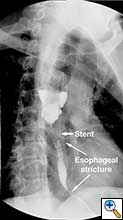

A 49 year old male presented to our institution with significant dysphagia and a 40 lb. weight loss secondary to a distal esophageal stricture. The patient had ingested lye 4 years previously and required partial gastrectomy, gastrojejunostomy, and partial colectomy at an outside institution at that time. His symptoms of dysphagia had progressively worsened despite repeated dilations and placement of an esophageal stent (Figure 1). Surgical reconstruction was therefore felt to be indicated. Preoperative computerized tomography angiogram did not clearly display the blood supply to the stomach, but did show that the colonic vasculature was adequate for use as a conduit if needed.

The abdomen was temporarily closed, and the patient was placed in left lateral decubitus position. A right posterolateral thoracotomy was made in the sixth intercostal space. After mobilization of the esophagus, it was divided one centimeter distal to the azygous vein, and the stent in the proximal esophagus was removed. After the stent was removed an esophagoscopy revealed normal esophageal mucosa and no injury or stricture of the proximal esophagus.